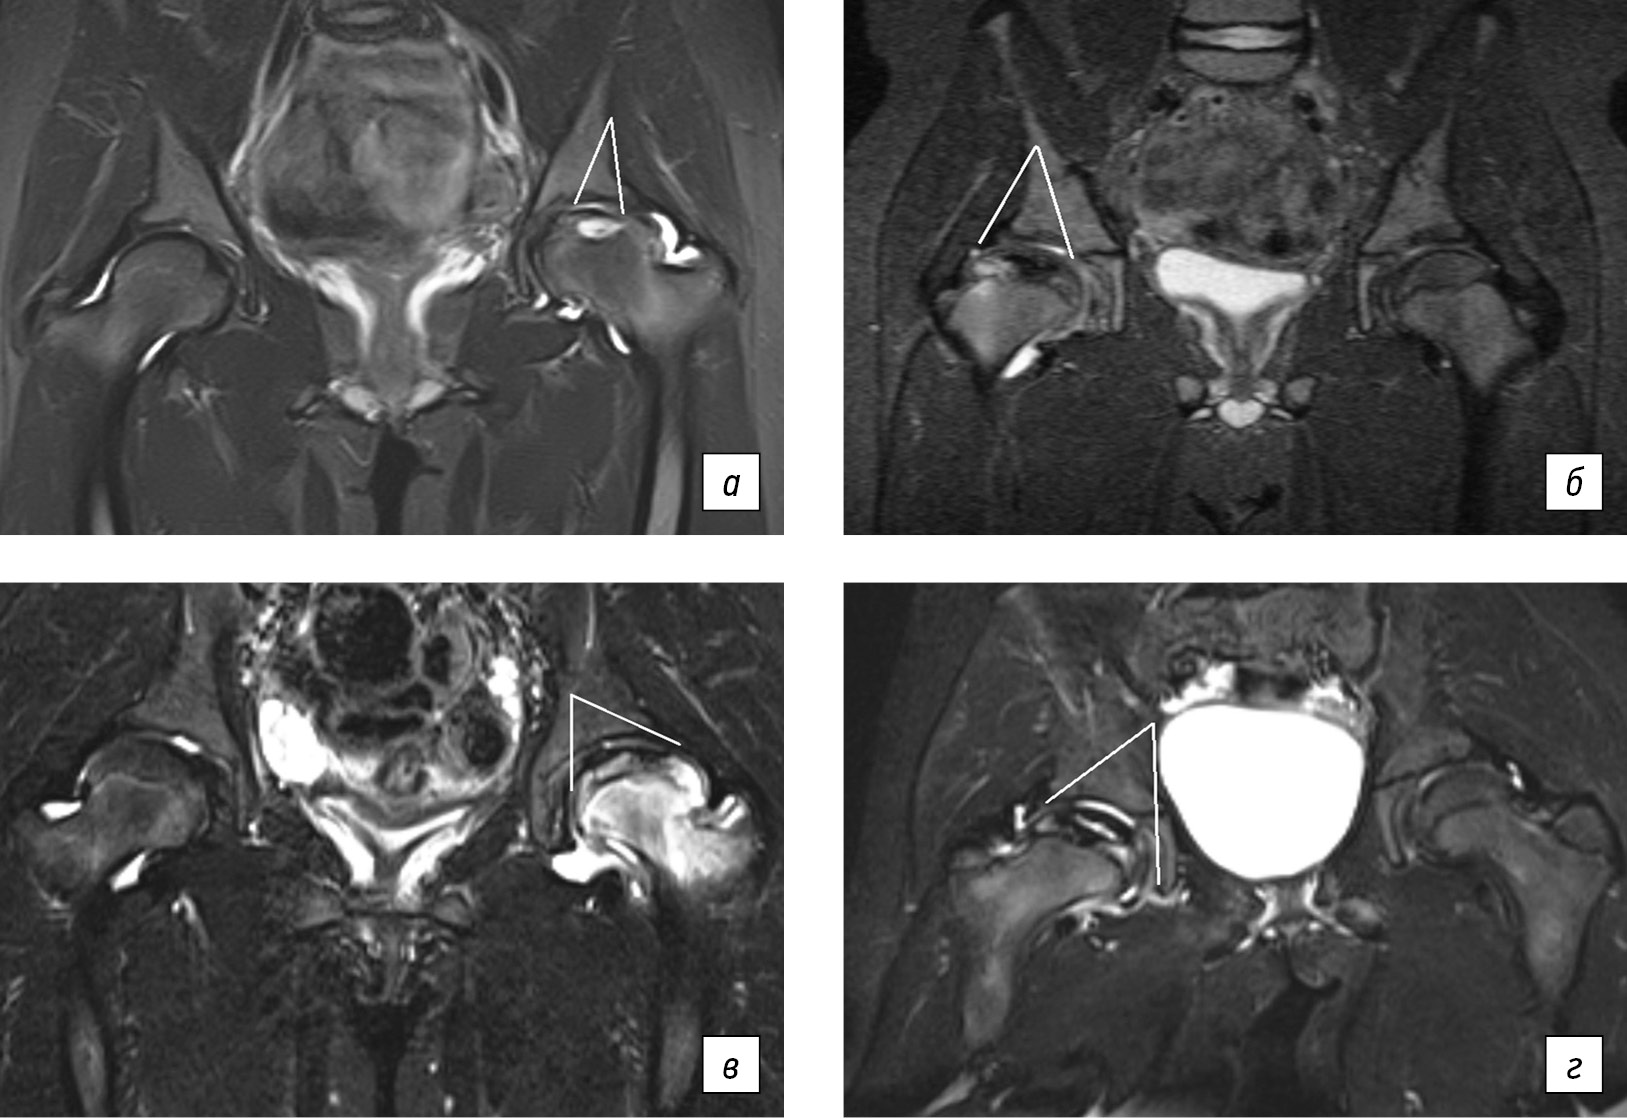

В исследование включены 14 детей (71,4 % девочки) с БЛКП, сопровождающейся признаками остеоартрита, которые получали лечение в НМИЦ детской травматологии и ортопедии им Г.И. Турнера в период 2022–2024 гг. На момент включения в исследование у всех детей диагностирована БЛКП в стадии импрессионного перелома, течение которой сопровождалось МР-признаками трабекулярного отека костной ткани и «активного» хронического синовита (рис. 1). Все дети имели артрит, торпидный к терапии НПВС, длительностью не менее 3 мес. Протокол лечения включал применение пяти последовательных инфузий препарата из группы бисфосфонатов — ибандроновой кислоты. Доза ибандроновой кислоты варьировала в зависимости от возраста и составила для детей до 7-летнего возраста 1,0 мг, старше 7 лет — 1,5 мг на инфузию. Инфузии ибандроновой кислоты осуществляли с интервалом 3 мес. БФ-терапию в обязательном порядке включали в структуру комплексного восстановительного лечения, которое состояло из лечебной гимнастики, противовоспалительных физиотерапевтических процедур, а также соблюдения ортопедического режима с исключением осевой нагрузки на пораженную конечность. Эффективность и переносимость терапии оценивали по результатам динамического наблюдения за пациентами через 3, 6, 9, 12 и 18 мес. от начала терапии. Клиническая часть протокола исследования предполагала объективный осмотр пациента, определение степени ограничения амплитуды движений в тазобедренном суставе, оценку выраженности болевого синдрома согласно визуальной аналоговой шкале боли (ВАШ), суставному индексу боли Ричи (RAI) и их динамики [15].

Рис. 1. Магнитно-резонансная томограмма: II стадия остеохондропатии головки бедренной кости слева с признаками остеоартрита; в режиме STIR определяются обширная зона деструкции головки бедренной кости, реактивный трабекулярный отек головки и шейки, явления хронического синовита

Для оценки воспаления тазобедренного сустава по шкале SCORING OF HIP MRI FOR JIA определяли степень утолщения синовиальной оболочки и наличие выпота. Измерения проводили на T2 STIR в коронарной плоскости два рентгенолога. При подсчете МР-признаков воспаления использовали градацию от 0 до 3, где 0 — отсутствие выпота и утолщения синовиальной оболочки; 1 — минимальное скопление выпота в капсуле сустава; 2 — умеренное скопление синовиальной жидкости с растяжением капсулы сустава и реакцией синовиальной оболочки; 3 — значительное скопление синовиальной жидкости с растяжением капсулы сустава и пролиферацией синовиальной оболочки (рис. 2).

Рис. 2. Магнитно-резонансная томограмма: признаки различной степени выраженности синовита тазобедренного сустава у детей с болезнью Легга – Кальве – Пертеса. В режимах STIR представлены: минимальное скопление выпота в капсуле сустава (а); умеренное скопление синовиальной жидкости с растяжением капсулы сустава и реакцией синовиальной оболочки (б, в); значительное скопление синовиальной жидкости с растяжением капсулы сустава и пролиферацией синовиальной оболочки (г)